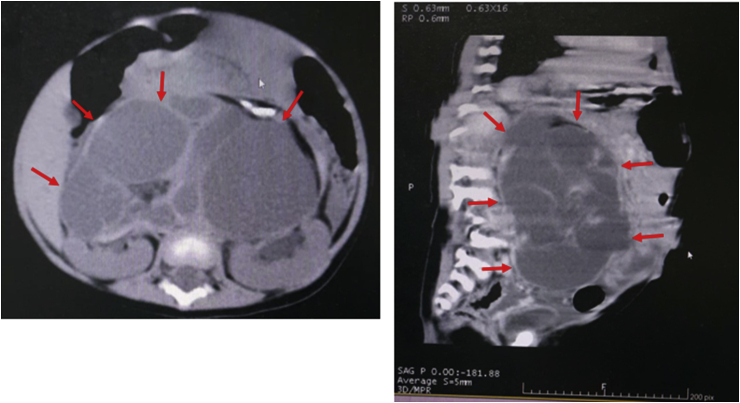

One week after the surgical excision, the patient became jaundiced, had pale stool, dark urine and had become malnourished. Due to no improvement after conservative management in the previous hospital, she was referred to our hospital. Her laboratory findings were total bilirubin of 14.17 mg/dL, direct bilirubin of 12.24 mg/dL, gamma glutamyl transferase of 1157 U/L, and alkaline phosphatase 187 U/L. Abdominal CT scan showed a CC that caused dilatation of the proximal CBD, common hepatic duct, and intrahepatic bile duct (Fig. 2a).

We decided to perform an explorative laparotomy and found a CC with diameter of 5 cm (Fig. 2b). We, then, conducted a Roux-en-Y hepaticojejunostomy. Histopathological findings showed walls that consisted of thick fibrous tissue and focal columnar epithelium, confirmed as CC (Fig. 2c).